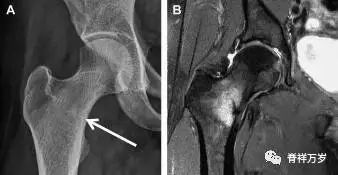

股骨近端骨折

股骨颈骨折常发生在老年人,头下型骨折最常见,但是当股骨外旋或有明显的关节炎骨赘形成时,骨折较难发现。此外,肥胖和骨量减少增加髋部 X 片诊断难度,所以需格外注意。

因骨结构重叠影响,股骨转子骨折发生轻度移位时亦很难发现,加做一个不同角度的 X 线片有助于诊断(图 6)。

图 6 摔倒后股骨大转子骨折。A 正位片初步检查未发现明显骨折,进一步检查发现大转子上方皮质中断(箭头)。B 蛙式侧位片示骨折分离,尤其是后方(箭头)。初步检查时忽视了这一点,是因为股骨颈未能充分显示